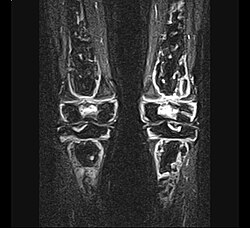

| Aseptische Knochennekrose - coronale MRT (STIR-Sequenz) einer aseptischen Knochennekrose mit Befall des distalen Femurs und der proximalen Tibia beidseitig bei einem 13-jährigen Kind mit akuter lymphatischer Leukämie (ALL) . | Eigenes Werk | Christaras A | Datei:AON knee (tibia and femur) - MR Coronal STIR - child 13 yrs after ALL - 01.jpg | |